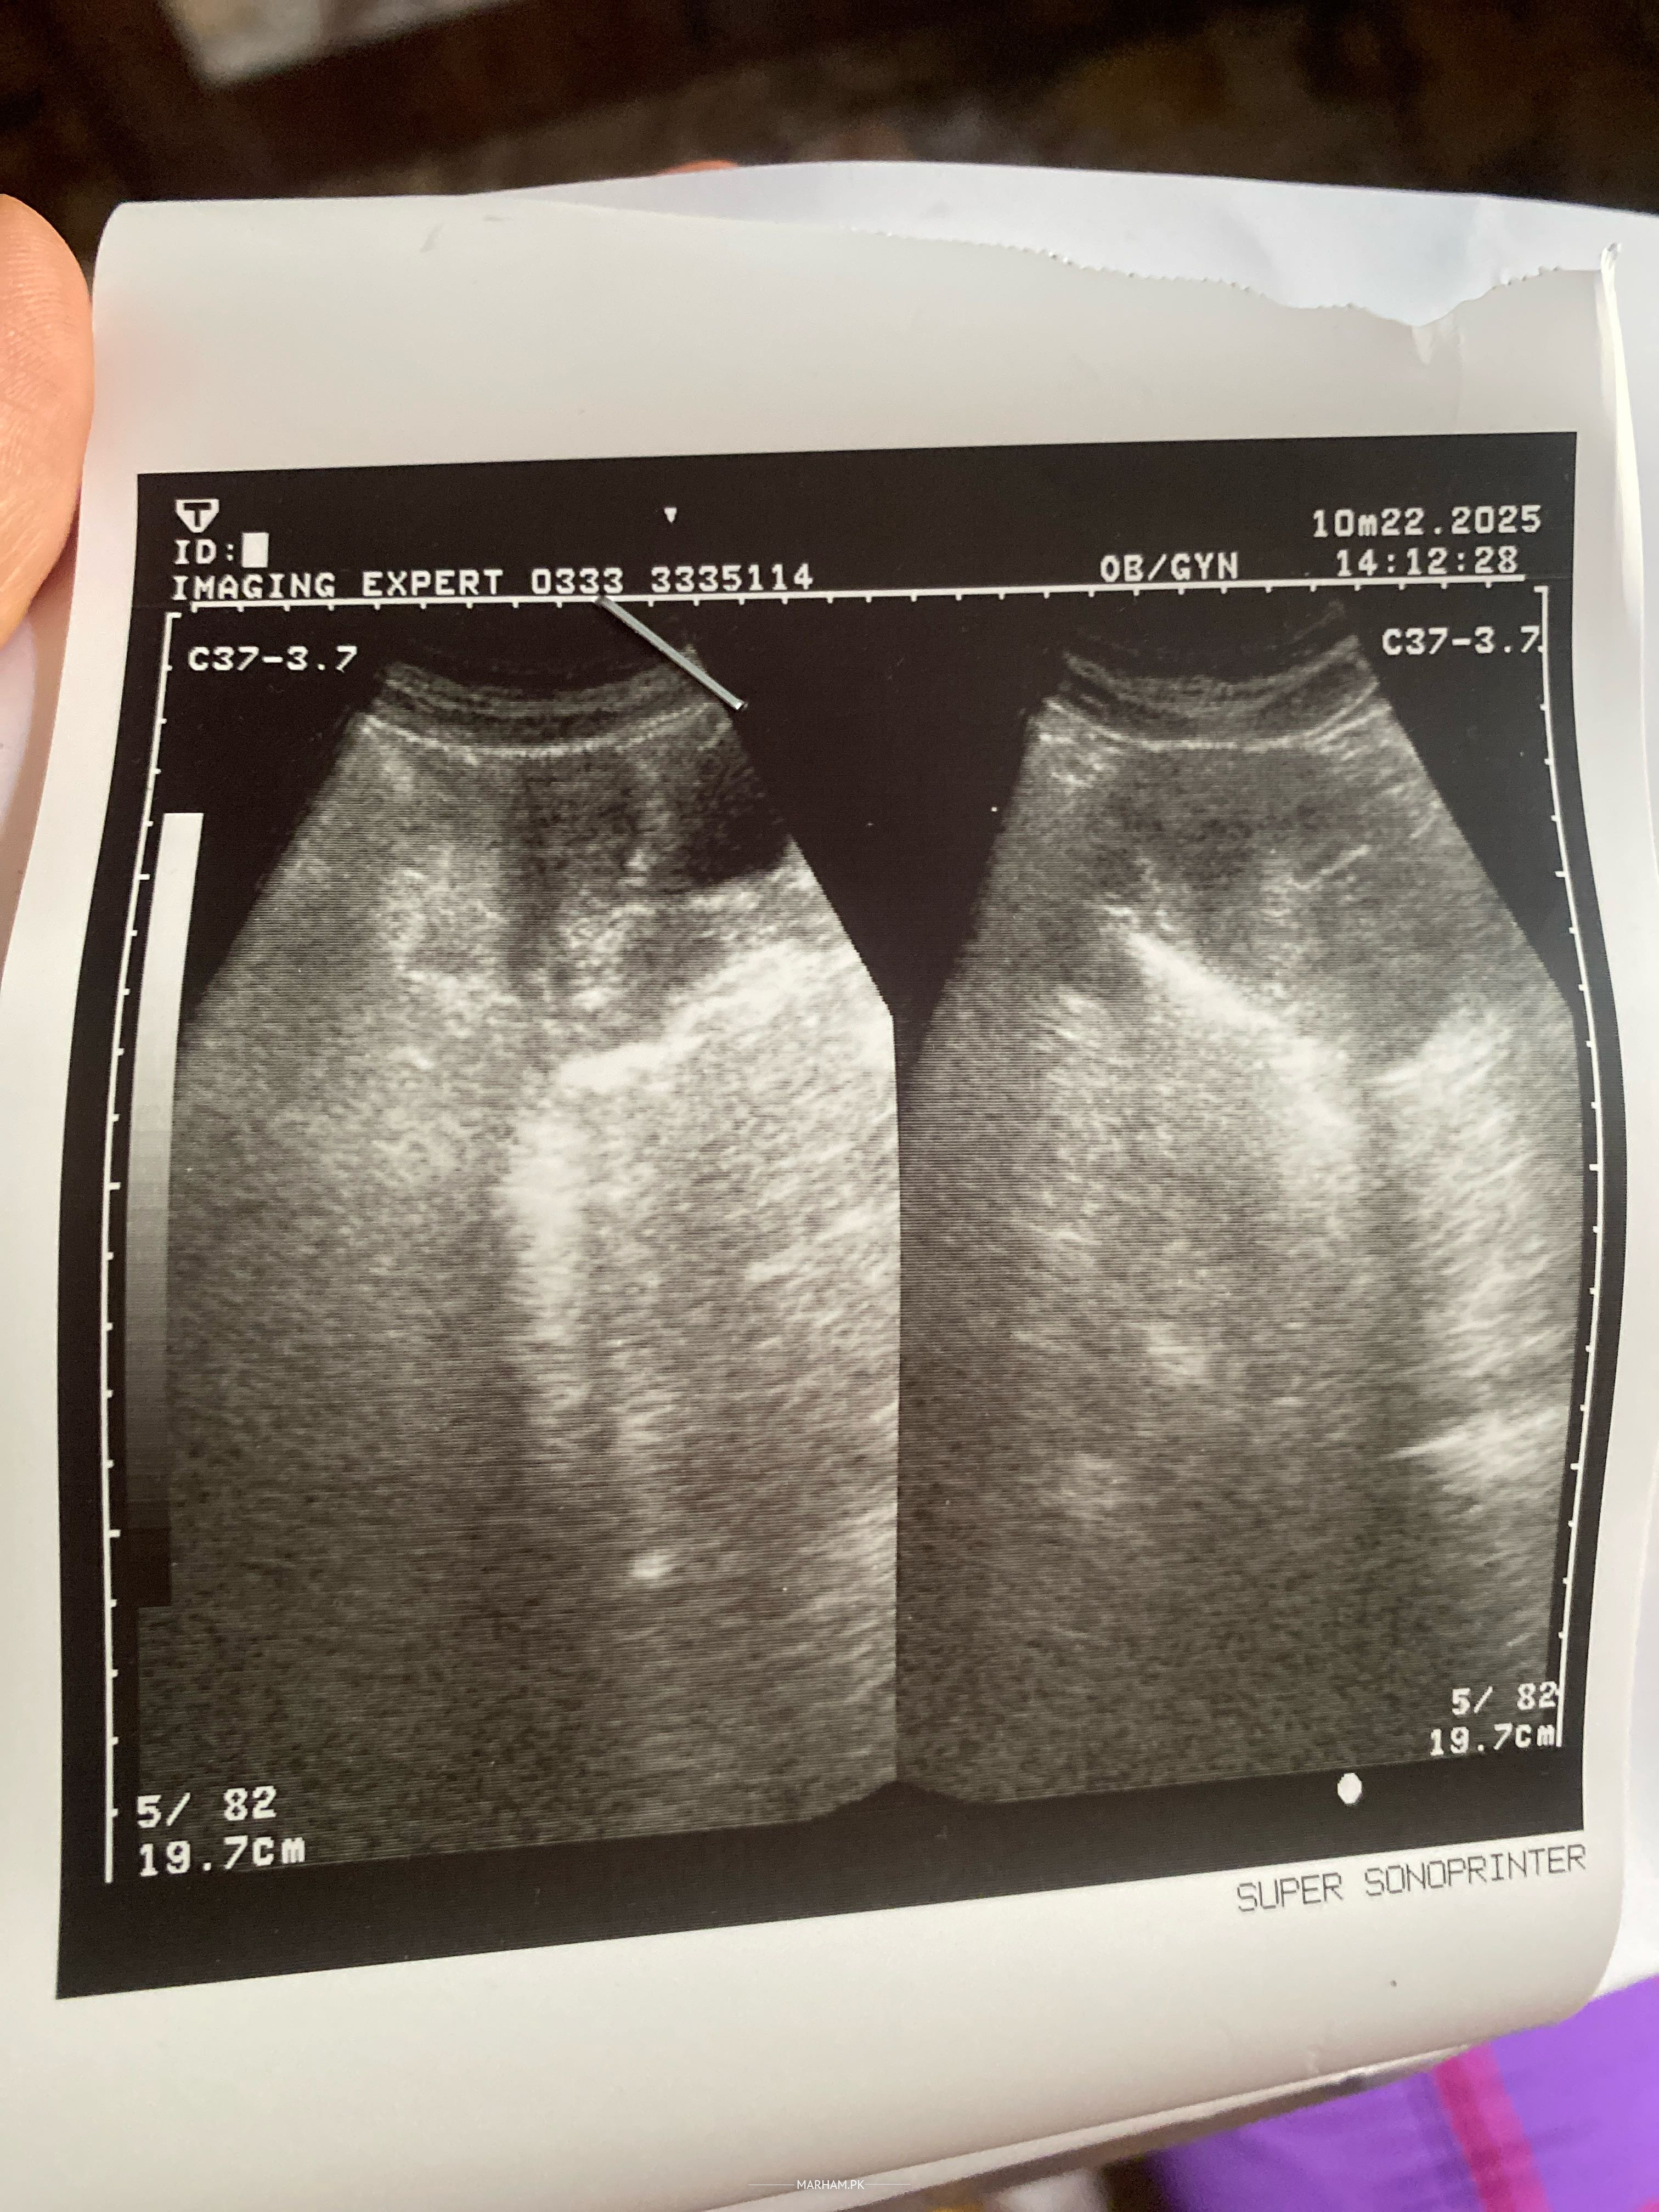

Your scan is normal. Lsometimes hormones can be imbalance due to anxiety tension and other factors.Take rest , maintain your diet . And answer me some more questions . Do you have any burning while you’re passing urine? And lower abdominal discomfort ?

* **See a Doctor:** The most important thing is to see a doctor or gynecologist. They can perform an examination, ask about your medical history, and order tests (like blood tests, ultrasound, or other imaging) to determine the cause of the spotting. The image you provided appears to be an ultrasound. The doctor will be able to interpret the results.